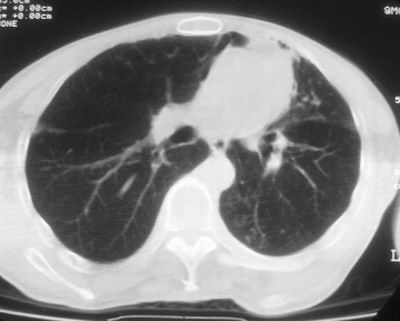

标题: CT11864:男,47岁,反复咳嗽、咯痰、咯血3年,请分析. [打印本页]

患者,男,47岁,反复咳嗽、咯痰、咯血3年,再发5天。痰培养未找到真菌、抗酸杆菌、癌细胞。

左肺上叶体积明显缩小,其内见多发透光区,纵隔向左侧移位,左肺下叶多发班片状病灶,边界模糊,1左肺上叶先天肺发育不全,2左肺下叶肺炎,

左肺上叶结核伴肺纤维化,纵隔移位,左肺下叶感染性病变,建议抗炎抗结核后复查,双肺气肿.

1.左肺上叶慢纤空2.左肺下叶炎症

1)考虑为:左肺上叶肺结核(空洞形成),伴左下肺感染;不排除霉菌感染可能。2)肺气肿。

左肺上叶结核伴肺纤维化空洞形成并左肺下叶感染,纵隔牵拉移位,建议作进一步检查排除左侧肺霉菌感染可能。

左上肺发育不良并支扩,慢支肺气肿并感染。